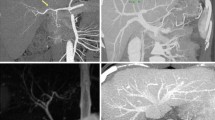

The assessment of a potential living donor begins with imaging studies to determine donor liver volume as well as the vascular and biliary anatomy of the liver. The donor patient is placed on a standard multi-detector CT scanner and a 1-2 mm incremental reconstruction is performed in both the arterial and venous phases. In our Institution, these images are sent to MEVIS distant service (Bremen, Germany) by an encrypted web transfer protocol for volumetric and anatomic analysis using proprietary FDA-approved software. This technology and the resulting information have been used successfully in the surgical planning of more than 4,500 LDLTs worldwide [1].

Total and segmental liver volumes are calculated using software-assisted image post-processing (SAIP) which has been proven to be the most accurate method for calculating these volumes, with a reported calculated versus actual volume difference of approximately 17.5 ml and a percentage of error of approximately 2.8 % [1, 2]. Since the software calculates the liver volume, which is a combination of liver parenchyma and blood filling the sinusoids, a correction factor of 0.9 is needed to predict the actual liver weight after procurement [3, 4]. Right and left graft volumes/weights are obtained therefore according to the desired transection line and inclusion/exclusion of the middle hepatic vein (Fig. 1). Left lateral segment and subsegmental volumes are also calculated when pediatric transplants are contemplated.

3D Modeling and Vasculature

Using a semi-automated process, the intrahepatic and extrahepatic vasculature is reconstructed three-dimensionally to obtain portal, arterial and hepatic venous territories. Vascular structures and the corresponding territories are color coded to provide a visual and quantitative (volume) representation of liver segments (Fig. 2).

Three-dimensional (3D) reconstruction of hepatic and portal veins has been shown to be better than, or equivalent to, angiograms [5] in delineating anatomy. It also offers the advantage of having all the vascular structures represented in one 3D image. Hepatic venous 3D reconstruction identifies the exact outflow anatomy of the liver, the spatial relationship of main and segmental veins (important when considering different surgical reconstruction techniques) and more importantly, provides the surgeon with a precise estimation of the liver territories that would undergo venous congestion if the correspondent venous outflow was sacrificed. Such estimation is very important since outflow compromise is associated with impaired regeneration, biliary complications, and potentially small for size syndrome [6–8].

Assessment of venous congestion is crucial when considering right lobe grafts, the most commonly used graft in adult to adult LDLT. Right lobe grafts, in fact, share the venous drainage of the anterior segments (5 and 8) with the left lobe (segments 4a and 4b) by means of the middle hepatic vein, which can be either retained or excluded from the graft. Our preferred approach is to exclude the middle hepatic vein from the graft because it is safer for the donor. This approach, combined with 3D reconstruction and estimation of segment 5 and segment 8 volumes, allows for a precise estimate of the graft recipient body weight ratio (GRBW) and helps guide venous reconstruction on the recipient (for instance, when inferior segment 6 veins are present) (Fig. 3). The experience of some transplant groups provides evidence that the use of 3D modeling [9–11] can be a crucial tool when making surgical determination to involve the middle hepatic vein in right lobe grafts.

At our institution, contrast-enhanced multi-phasic CT angiography is used to assess vascular anatomy on all potential LDLT donors. T2-weighted MRCP is used to evaluate the biliary anatomy. All donors undergo intraoperative cholangiogram for anatomy confirmation and determination of the duct transection line. Once the MRCP is obtained, the images are fused with those obtained with the CT scan. Three-dimensional modeling allows the integration of all the relevant anatomical structures (portal vein, hepatic artery and bile duct) in one image along with the virtual parenchymal transaction line. The gallbladder (and other anatomical structures) can also be included in the model and used as a landmark for the establishment of the transection line. The interactive manipulation of this image prior to surgery helps simulate the changes in perspective experienced during the actual operation (mobilization and rotation of the liver), thus allowing the surgeon to better understand spatial relationships among critical structures during the different phases of the operation. Importantly, this serves to minimize intraoperative complications [16].

Our group recently developed a prototype of a human liver using 3D printing technology based on a patient’s individual CT scan and magnetic resonance imaging (MRI) [17••] (Fig. 4). This model was prospectively studied on three consecutive patient pairs (three donors and three recipients) who were evaluated and approved for LDLT at our Institution. Through direct comparative validation protocol, these models were shown to have very high accuracy, with a mean dimensional error of less than 4 mm for the entire model and less than 1.3 mm for vascular diameter (portal vein and its main branches, hepatic veins or hepatic artery) (Fig. 5).